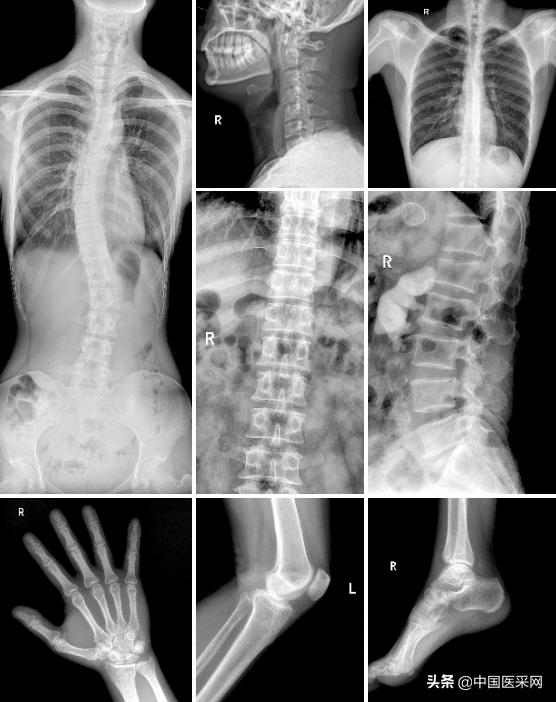

最后,该产品搭载了多款智能系统,如珠穆系列标配的全自动长骨拼接功能,可辅助脊柱畸形矫形治疗、康复检查。可为制定髋关节置换手术方案等提供更全面的信息。

此外,珠穆系列还配备了自动曝光控制(AEC)、限束器智能缩窗、专业尘肺检查等功能,使其能够适应骨科、外科、儿科、妇科等全科室的应用!优异的临床图像表现,不难看出安健科技在打磨产品时的诚意。